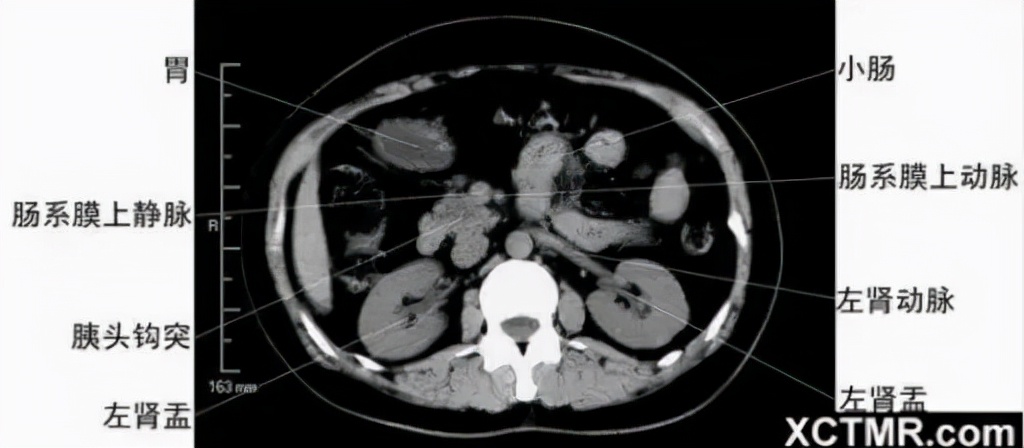

腹部CT